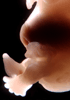

Carnegie Stage 22 (54 post-ovulatory days)

Most embryos at stage 22 are approximately 54 postovulatory days old and measure 25-27 mm in length. Distinguishing criteria for this stage include clear formation of the external ear, the hands begin to extend ventrally beyond the body wall, the fingers of one hand may overlap the fingers of the opposite hand, thickened eyelids just begin to cover the outer margins of the eye, and the superficial vascular plexus of the head now extends about three-quarters of the way above the eye-ear level.

Photographs